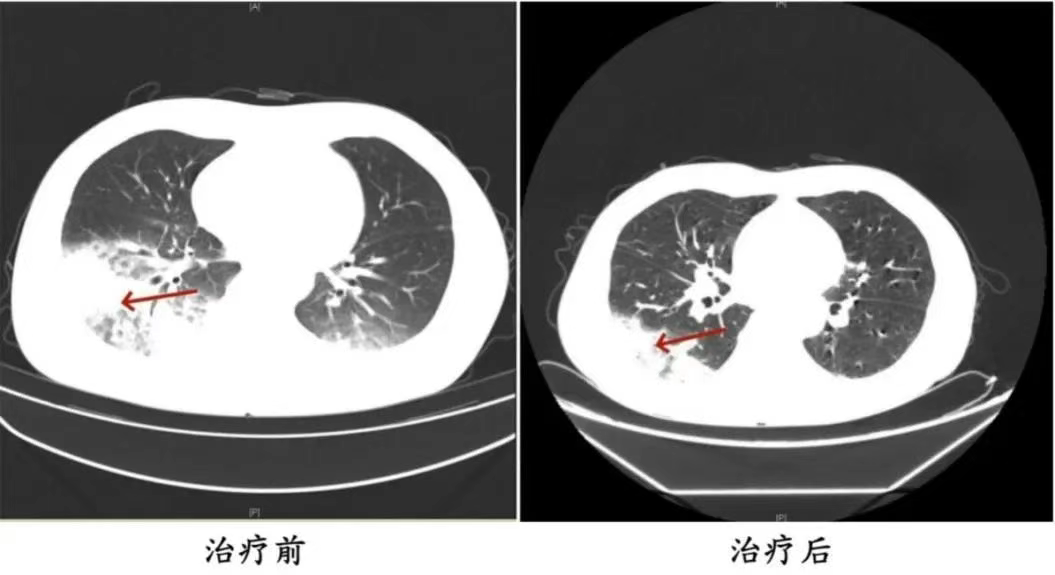

家人见状,立即将他送医。胸部CT显示李先生的左肺已出现大面积白色影像,几乎占据一半肺部。经过检测,最终确认是嗜肺军团菌肺炎。